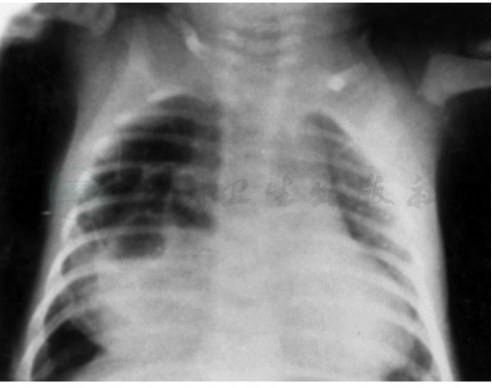

图1 肺囊肿

患儿,男,1个月。因咳嗽1周伴喘憋,右中叶多房性肺囊肿继发感染;2.5月+时手术证实囊肿大小7cm×5cm×4cm。X线显示右第3~6前肋前可见巨大多房性囊性肿物,其中有气液面及分隔薄壁。

孤立性液性囊肿呈一界限清晰的圆形致密阴影。孤立性含气囊肿呈一圆形或椭圆形薄壁的透亮空洞阴影,大者可占据半个胸腔。其周围肺组织无浸润,可见正常含气的肺或无气的肺不张阴影。如囊肿与支气管沟通,则可见薄壁而含有气液平面的囊肿影(图1)。如系多发性囊肿,可见多个环形空腔或蜂窝状阴影分布在一个肺叶内。支气管造影可以确定囊肿病变范围和位置。CT对于判断囊肿的部位、大小及邻近脏器的关系有帮助。大泡性囊肿与气胸的鉴别可作增强CT扫描,前者可见到肺血管影。血管造影有助于鉴别隔离肺。如肺囊肿位于后纵隔,出现食管压迫症状,吞咽困难时需作钡餐检查以了解肿物与食管的关系,并可鉴别膈疝。